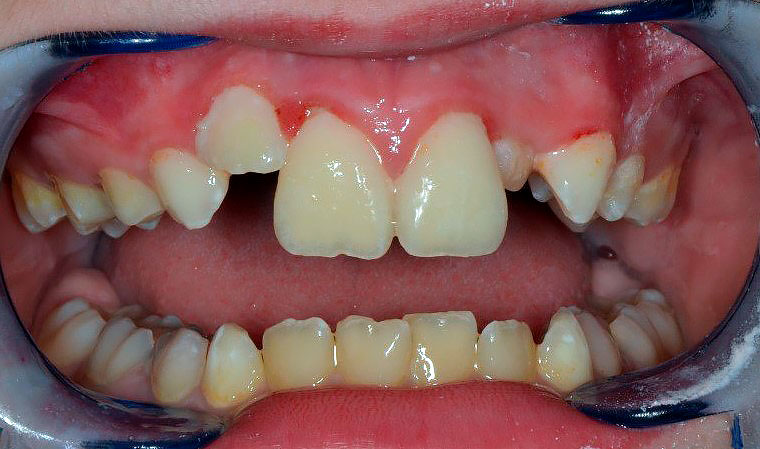

Осмотр полости рта: зубы 5.3, 6.3 прорезаны полностью, коронка интактная, подвижность отсутствует, зуб 1.2 в стадии прорезывания, имеет вестибулоположение, коронка интактная, подвижность отсутствует, зуб 2.2 в полости рта не прорезался. Зуб 6.4 в полости рта отсутствует, зуб 6.5 коронка интактная, подвижность отсутствует. Зубы 1.1, 2.1: визуализируется диастема, коронки зубов интактные, в цвете не изменены, патологическая подвижность 2 степени, перкуссия болезненная. Холодовая проба: положительная кратковременная реакция. При зондировании пародонтологическим зондом (вестибулярно и нёбно в трех точках) определяются патологические зубодесневые карманы глубиной до 13 мм. Гнойное отделяемое отсутствует. Краевая слизистая в области зубов 1.1, 2.1 гиперемирована. Фенотип десны во фронтальном отделе верхней челюсти толстый (Рисунки 1-3)

Рисунок 1. Клиническая картина в полости рта, после проведения местной анестезии.

Зубы 1.1, 2.1 подвижность отсутствует, диастема отсутствует, холодовая проба положительная. Определяются обильные отложения зубного налета. Окружающая слизистая гиперемирована. Признаки патологических десневых карманов отсутствуют. Признаки прорезывания зубов 2.2 и 2.4 (Рисунки 17, 18).

Рисунок 17. Клиническая картина через 6 месяцев после хирургического лечения.